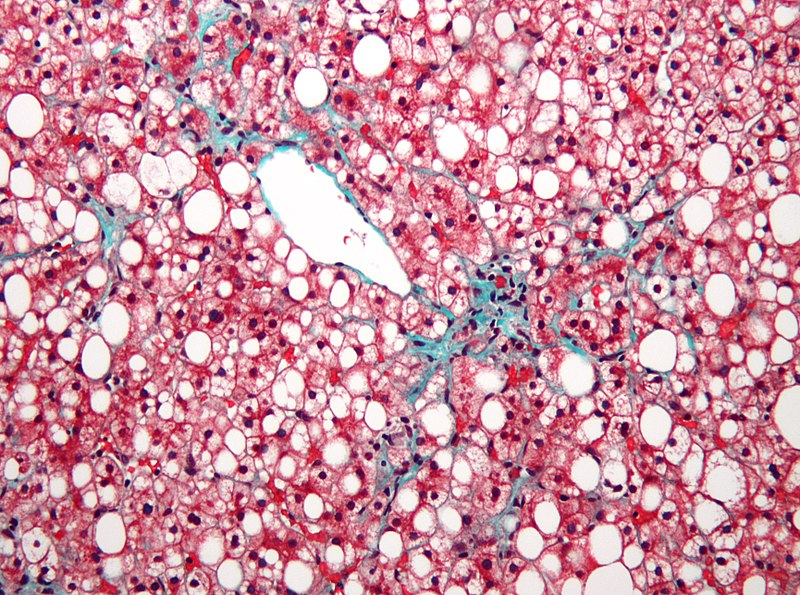

Cirrhosis is the last stage of liver damage and is marked by bands of fibrosis and hepatocyte regenerating nodules that disrupt the normal hepatic parenchyma.

Under the endothelial cells that line the sinusoids, stellate cells that are present in fibrosis are responsible for cirrhosis.

The buildup of fat in hepatocytes causes the liver to become heavy and greasy.

Cirrhosis is a consequence of long-term, chronic alcohol-induced liver damage that affects 10 – 20% of people who excessively drink alcohol.

Nonalcoholic fatty liver disease (NAFLD) is characterized by fatty changes, hepatitis, and/or cirrhosis that occur without the use of alcohol or any other recognized injury, yet it is linked to obesity.